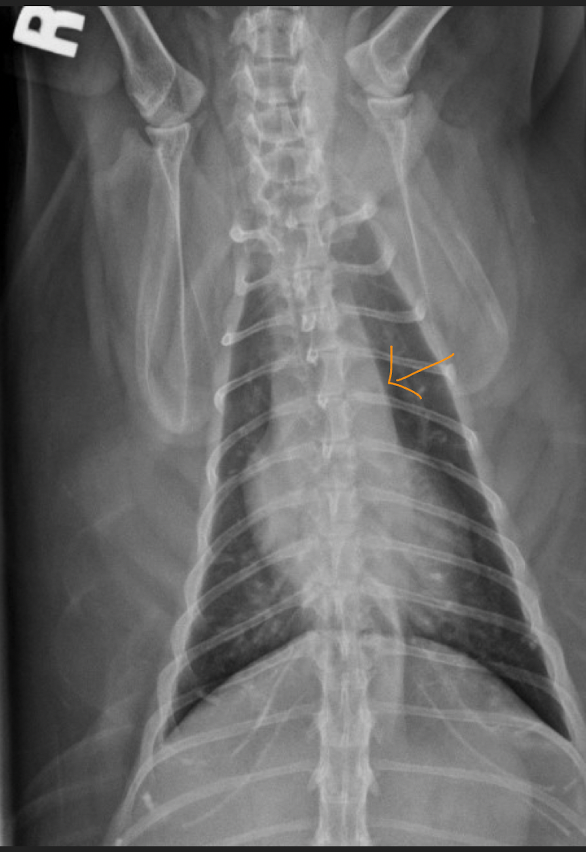

25

where are lymphnodes in this pt with medistinal lymphadenopathy

26

what is happening? ddx

cranial mediastinal mass- pushing everything **Thymus** →Neoplasia (Thymoma, Lymphoma); [↓Hemorrhage] **Lymph node** (sternal, cranial mediastinal)→ Neoplasia (Lymphoma) **Mediastinum / Adnexa** →Neoplasia (Sarcoma, Carcinoma); Cyst; [↓ Abscess, Granuloma, Hemorrhage]